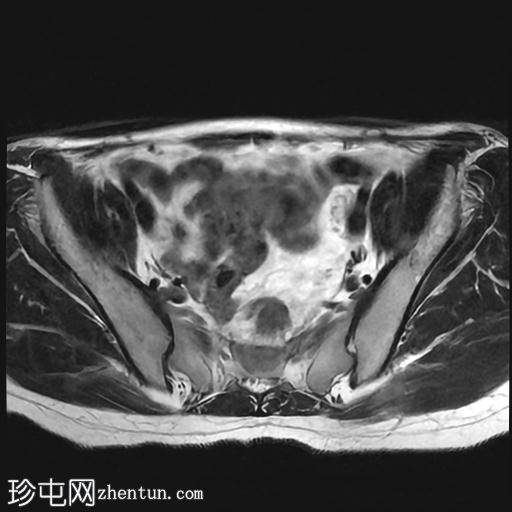

轴位

T2加权像

该宫颈癌体积较大,局部晚期,大小为22 x 40 x 42 mm,起源于宫颈左后外侧壁,向下延伸至阴道上三分之一处,位于宫颈中后外侧壁。

病变还累及左侧前外侧的宫旁组织。

左侧髂内静脉分叉下方可见一异常信号淋巴结肿大,最大短轴直径(SAD)为 8 mm。该淋巴结在弥散加权成像(DWI)上显示水限制,并有对比增强。

影像学检查结果提示,根据 FIGO 分期系统,该患者为宫颈癌 IIIC1 期。

宫颈肿块活检的组织病理学报告显示为宫颈鳞状细胞癌,具体来说是角化型。